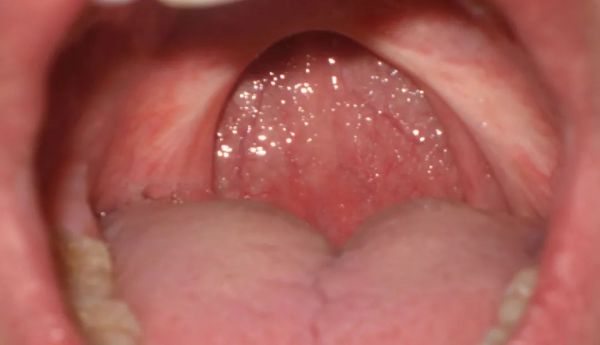

如果打呼嚕跟上氣道狹窄有一定的關(guān)系,而這個(gè)狹窄是局部的,那手術(shù)處理局部狹窄就是很好的辦法。比如那些明顯扁桃體肥大、腺樣體肥大引起的打呼嚕,手術(shù)切除就能很好地解決問題。

可惜多數(shù)人的狹窄并不是局部,手術(shù)就難有用武之地了。最近也流行有一種復(fù)雜的懸雍垂-腭-咽成形術(shù),試圖用手術(shù)干預(yù)其他人的打呼嚕。但從目前的使用情況看,效果維系時(shí)間較短。

手術(shù)之后的咽喉部

圖片來源:wikipedia

點(diǎn)評:對少數(shù)明確是扁桃體等局部問題引起的打呼嚕,手術(shù)最為推薦。